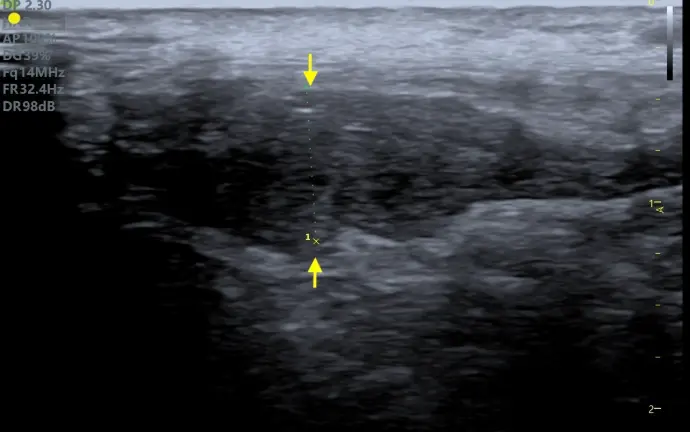

Grâce à l’utilisation d’une sonde linéaire de haute fréquence, garantissant une définition optimale, il est possible d’évaluer échographiquement de nombreuses structures superficielles : région cervicale, appareil musculo-tendineux, nerfs (nerf sciatique, plexus brachial …), hernies …